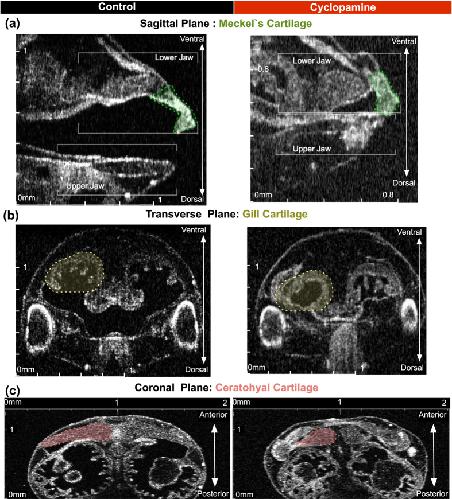

CFAP45, a heterotaxy and congenital heart disease gene, affects cilia stability., Deniz E, Pasha M, Guerra ME, Viviano S, Ji W, Konstantino M, Jeffries L, Lakhani SA, Medne L, Skraban C, Krantz I, Khokha MK., Dev Biol. July 1, 2023; 499 75-88. |

Pleiotropic role of TRAF7 in skull-base meningiomas and congenital heart disease., Mishra-Gorur K, Barak T, Kaulen LD, Henegariu O, Jin SC, Aguilera SM, Yalbir E, Goles G, Nishimura S, Miyagishima D, Djenoune L, Altinok S, Rai DK, Viviano S, Prendergast A, Zerillo C, Ozcan K, Baran B, Sencar L, Goc N, Yarman Y, Ercan-Sencicek AG, Bilguvar K, Lifton RP, Moliterno J, Louvi A, Yuan S, Deniz E, Brueckner M, Gunel M., Proc Natl Acad Sci U S A. April 18, 2023; 120 (16): e2214997120. |

Xenopus Tadpole Craniocardiac Imaging Using Optical Coherence Tomography., Deniz E, Mis EK, Lane M, Khokha MK., Cold Spring Harb Protoc. June 7, 2022; 2022 (5): Pdb.prot105676. |

Analysis of Craniocardiac Malformations in Xenopus using Optical Coherence Tomography., Deniz E, Jonas S, Hooper M, N Griffin J, Choma MA, Khokha MK., Sci Rep. February 14, 2017; 7 42506. |